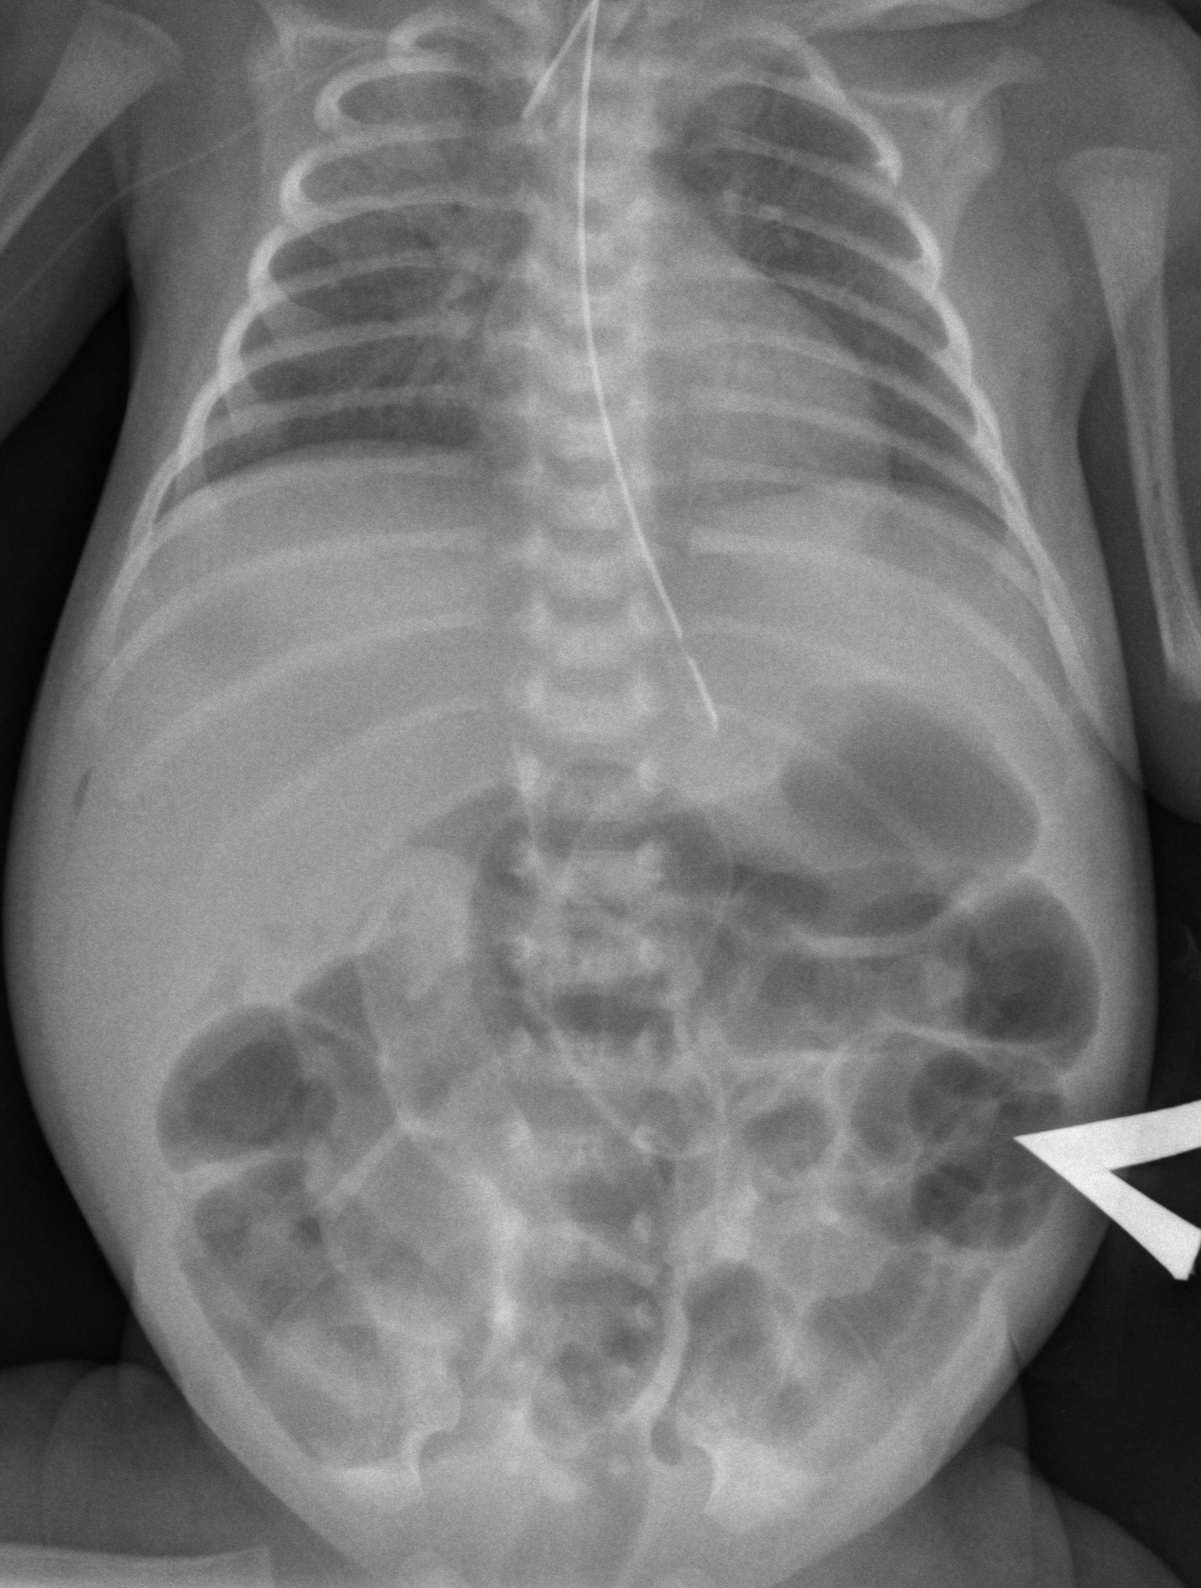

Нормы обзорной рентгенографии брюшной полости